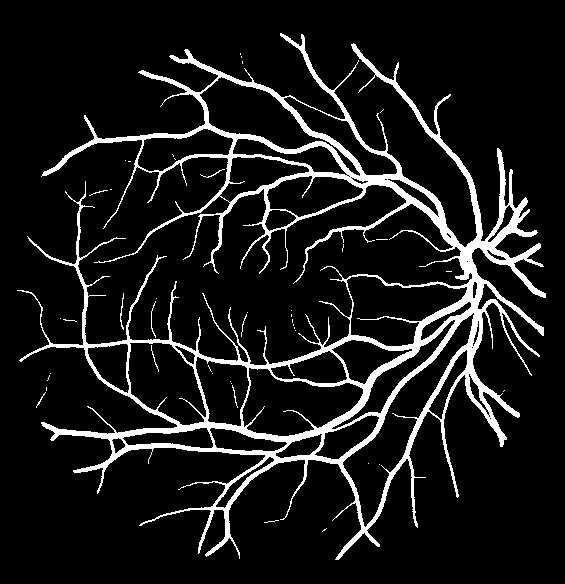

VI-A Retinal Artery and Vein Segmentation

As reported in Table IV, we compared the SegRAVIR model against competing deep learning-based segmentation approaches on the RAVIR dataset. Evidently, SegRAVIR outperforms these methods as judged by all metrics for artery and vein classes with a healthy margin. In terms of Dice score, SegRAVIR outperforms CE-NET, IterNet and AG-Net by , and for artery segmentation and by , and for vein segmentation, respectively. Fig. 4 presents a qualitative comparison of the semantic segmentation outputs of SegRAVIR, CE-Net, and U-Net. Specifically, SegRAVIR yields more accurate vessel topology (i.e., thickness and orientation) segmentation with higher pixel-wise classification accuracy.